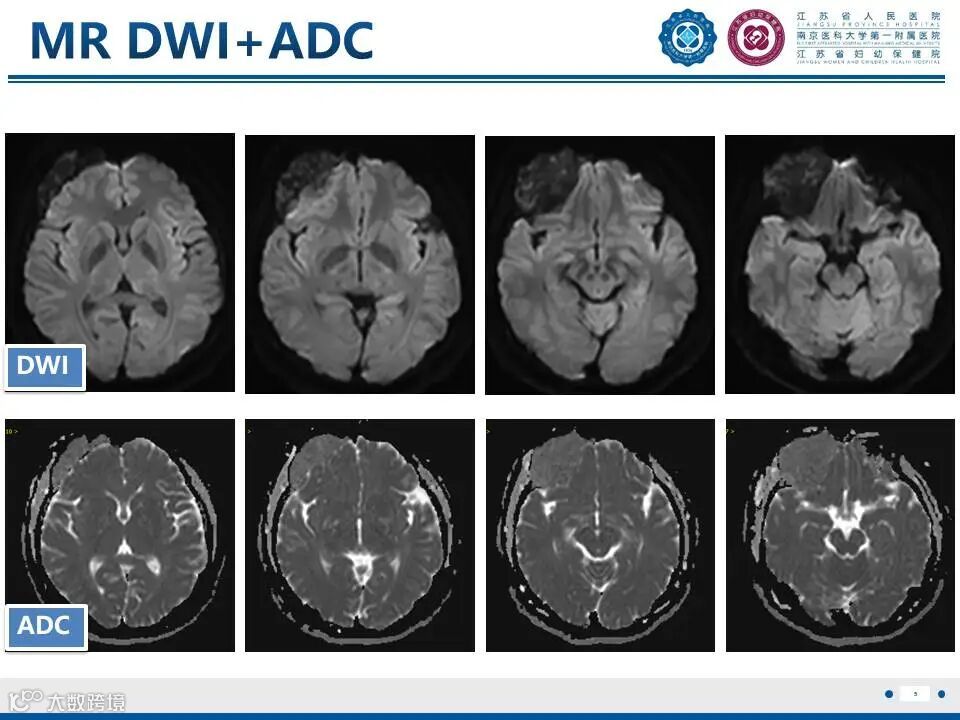

来源:江苏省人民医院放射科